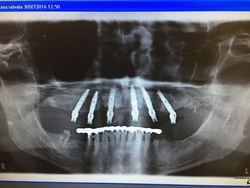

L’intervento si è concluso con successo con la messa in opera di una protesi a carico immediato Precostituita tipo all-on-six, impiegando una componentistica protesica progettata appositamente per facilitare l’istallazione di questi manufatti anche nelle situazioni più difficili.

Le conclusioni finali e le verifiche radiologiche hanno confermato l’efficenza del metodo dei materiali impiegati oltre che la grande esperienza del Clinico relatore, con grande apprezzamento dei partecipanti e degli organizzatori del corso.